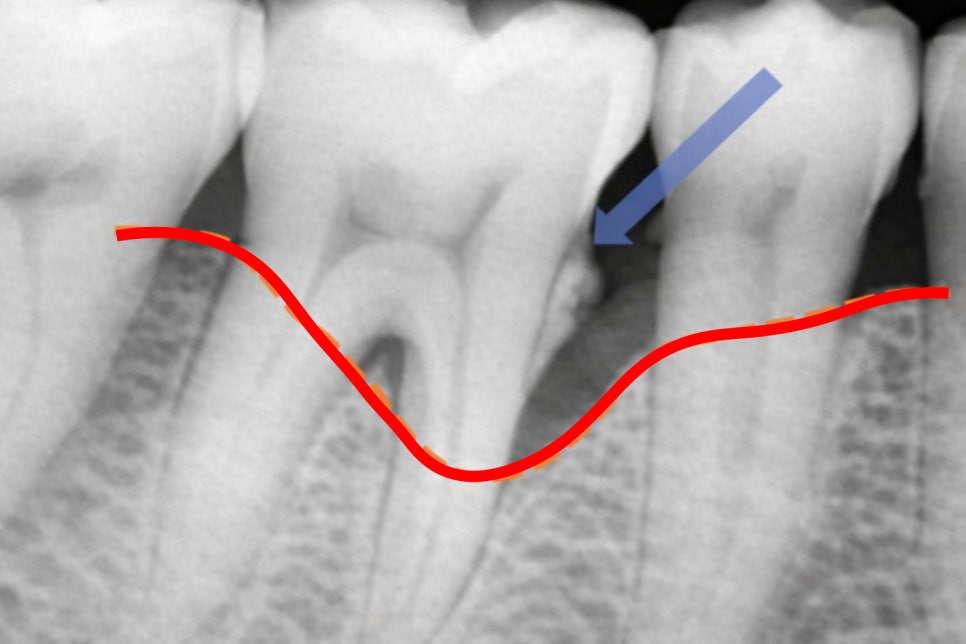

오랜 기간 쌓이게 되면 치주 조직에

지속적인 자극과 염증 반응을 유발하며

초기에는 잇몸이 붓고 피가 나는

치은염에 그치지만,

문제는 치은염을 방치했을 때이며

관리가 제대로 이루어지지 않는다면

치아를 지지하는 치조골까지 서서히

녹아내리는 치주염으로 발전하게 됩니다.

치주염이 진행되면 멀쩡해 보이던

치아조차 흔들리다 결국

발치에 이르는 상황이 발생합니다.